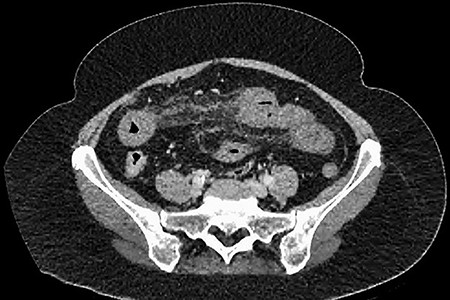

A 61-year-old female presented to a regional hospital with a 3-week history of intermittent diarrhoea, vomiting and generalized abdominal pain. She had a diffusely tender abdomen but was not peritonitic, and was shocked with a heart rate of 110 beats per minute, blood pressure of 89/45 mmHg and was peripherally cool. Her blood tests revealed a lactate of 7.2 mmol/L, which worsened to 7.8 mmol/L during resuscitation with intravenous fluids, and white cell count was 30.9 × 109/L, with an international normalized ratio (INR) of 1.4. She had an acute kidney injury with a creatinine of 119μmol/L and estimated glomerular filtration rate (eGFR) of 43 mL/min/1.73m2. Computed tomography (CT) revealed extensive thickened loops of non-enhancing small bowel with pneumatosis, moderate free fluid and a large splenic infarction. There was extensive thrombosis of the splenic vein and superior mesenteric vein extending into the portal vein to the level of the porta hepatis. Her background history included factor V Leiden and protein S deficiency, for which she had been non-compliant with warfarin during this illness. She had no surgical history (Figs. 1–5).

CT showing an area of splenic infarction due to venous ischaemia.